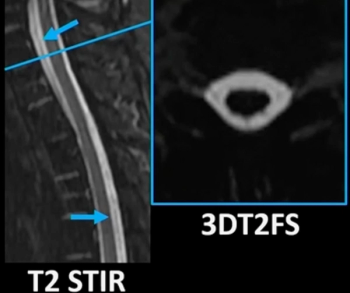

In a recently published review, radiology researchers from the University of Wisconsin discussed the potential and key considerations for applying accelerated magnetic resonance imaging (MRI) protocols in the assessment of emergent and urgent conditions.